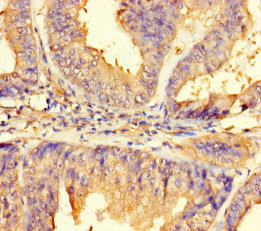

Immunohistochemistry of paraffin-embedded human endometrial cancer using CSB-PA889191LA01HU at dilution of 1:100